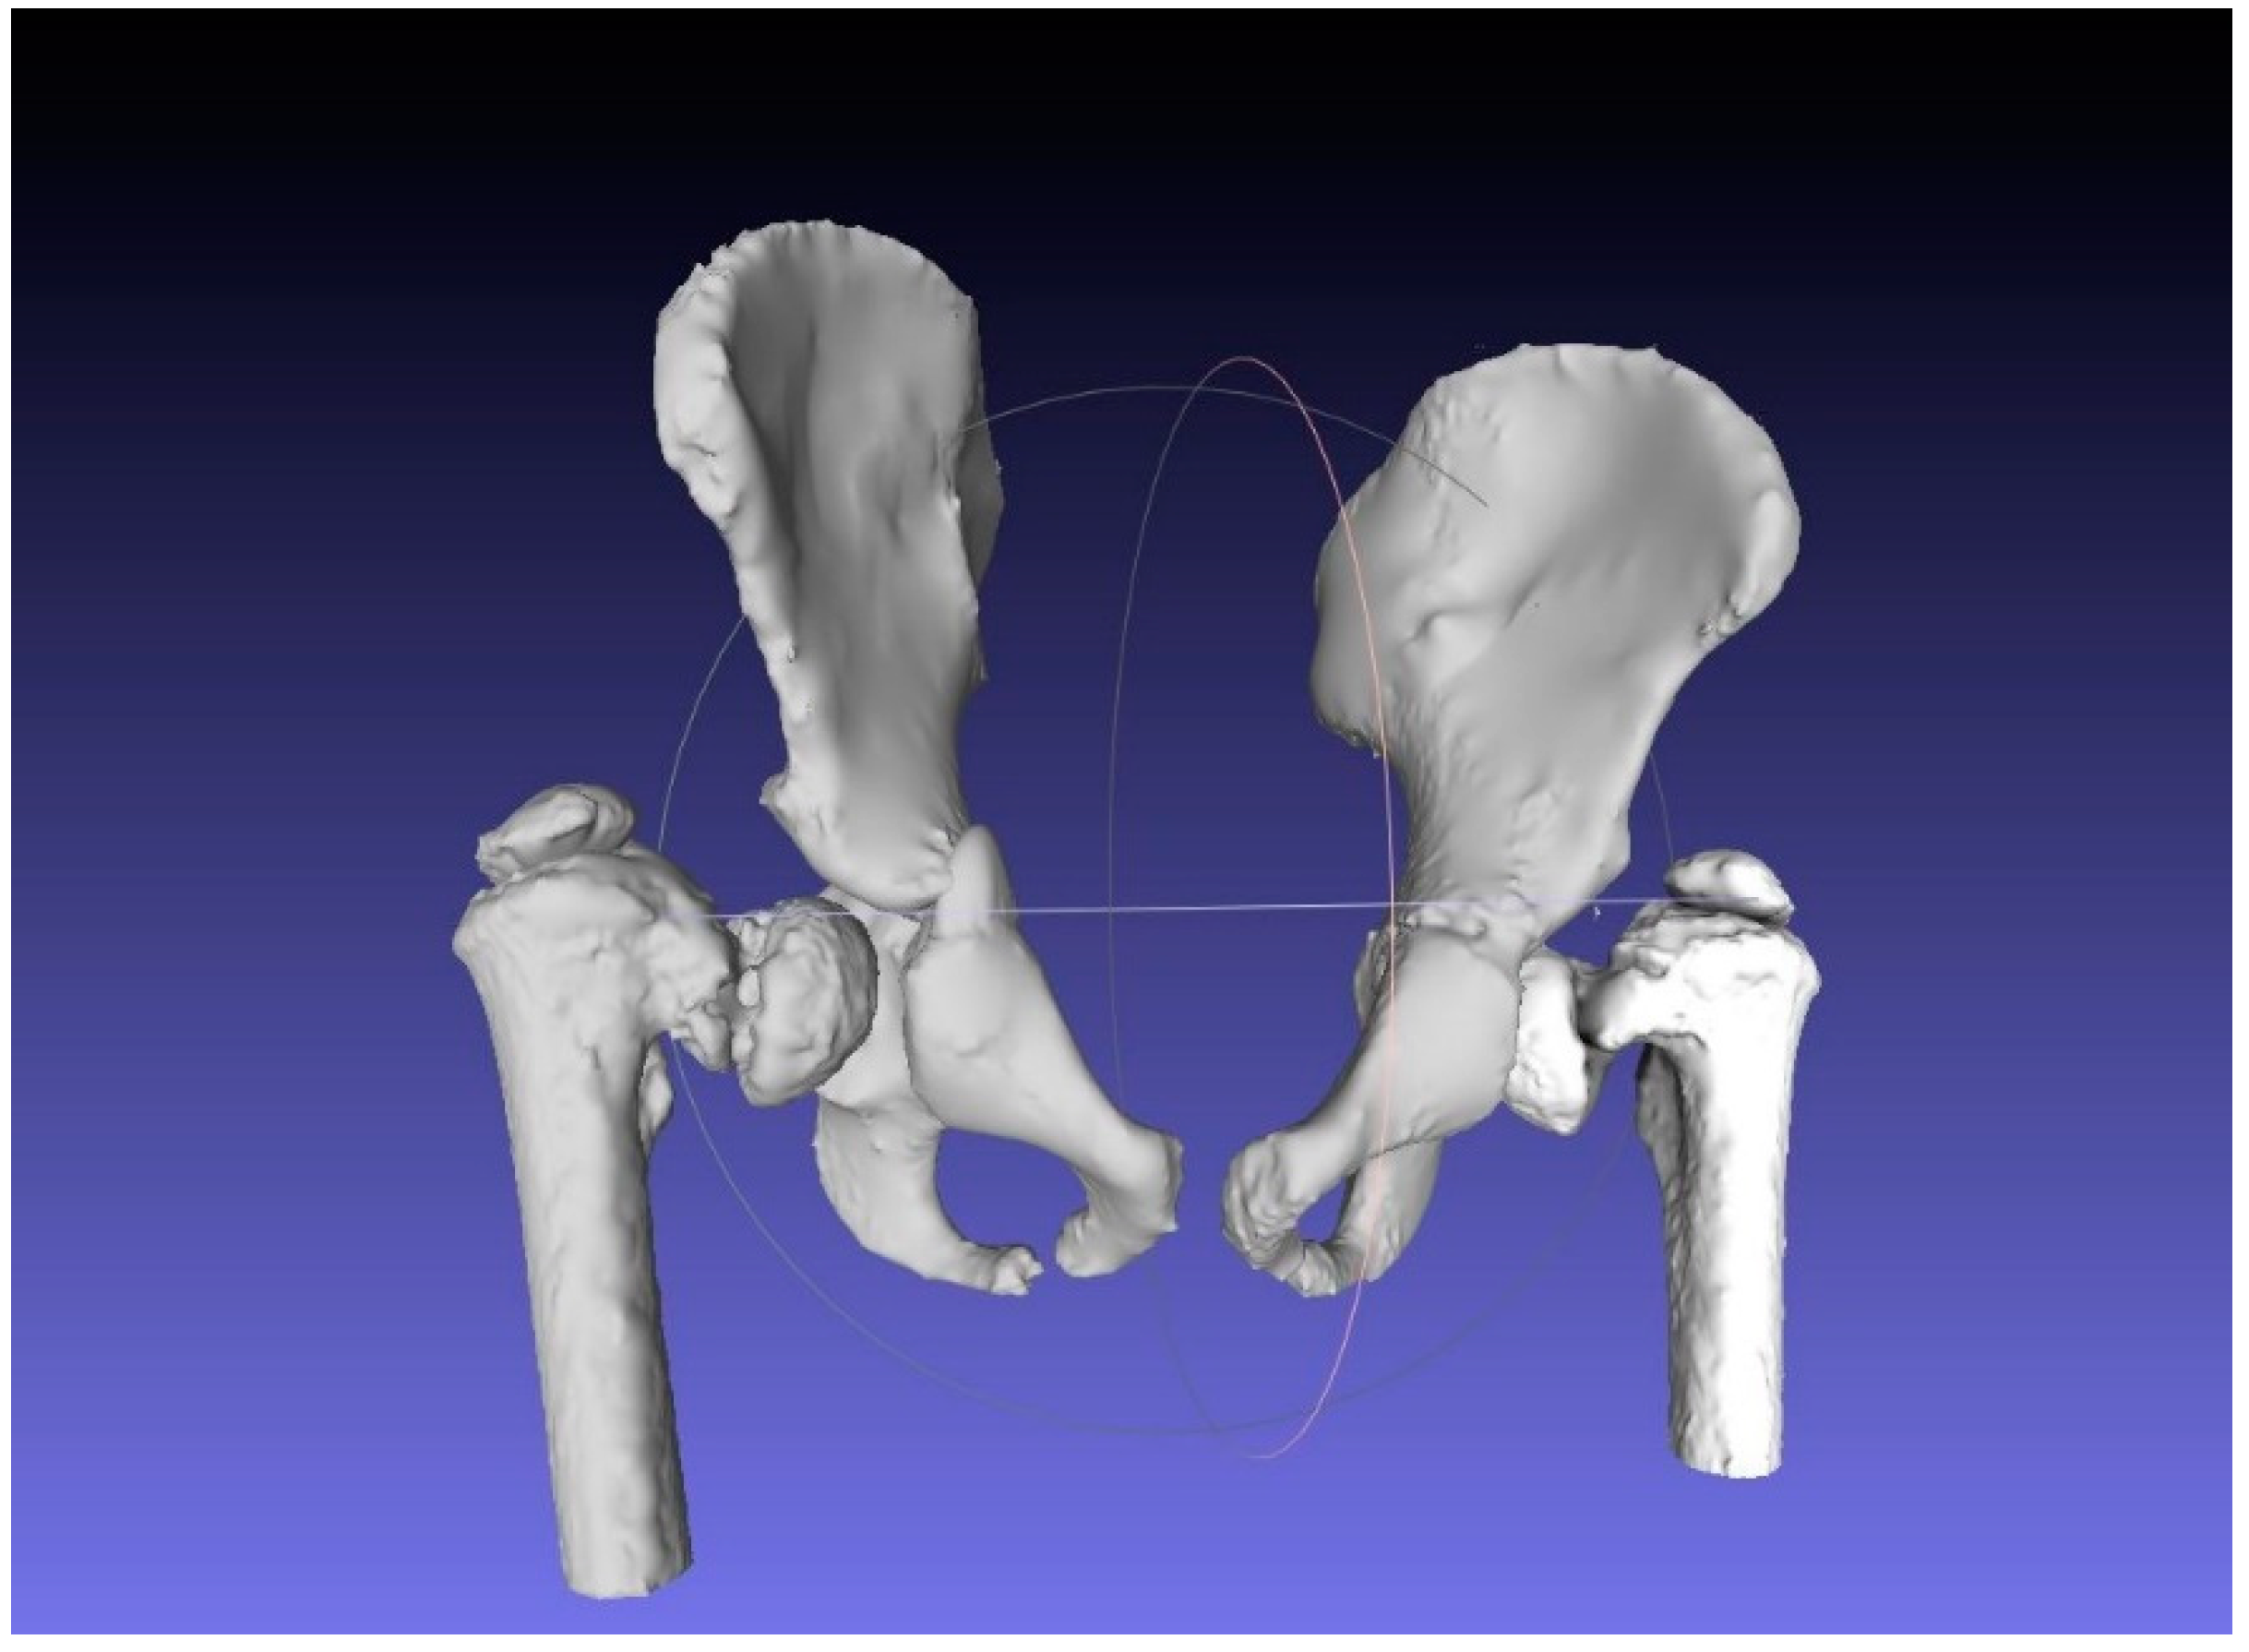

2.1. Case Study

2.2. CAM and CAD-CAT

2.3. CASS and CCG Design